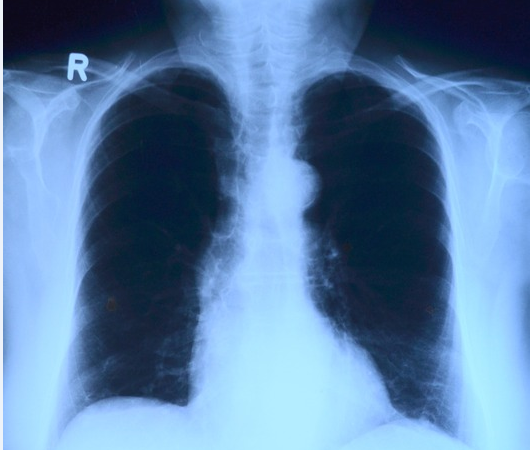

Una mujer que padecía de fibrosis múltiple desarrolló un cáncer después de haber recibido, mediante un trasplante, los pulmones de una fumadora en Francia. Así lo revela un estudio publicado en la revista 'Lung Cancer', donde se alerta de los riesgos de los trasplantes de órganos.

En 2017, la paciente tuvo que ser ingresada en el citado hospital, en la unidad de oncología torácica, y dos meses más tarde falleció como consecuencia de un cáncer de pulmón.

"El breve plazo entre el trasplante de pulmones y la aparición de la primera anomalía radiológica sugiere que la carcinogénesis comenzó en vida de la donante", aseguraron los especialistas responsables del estudio.